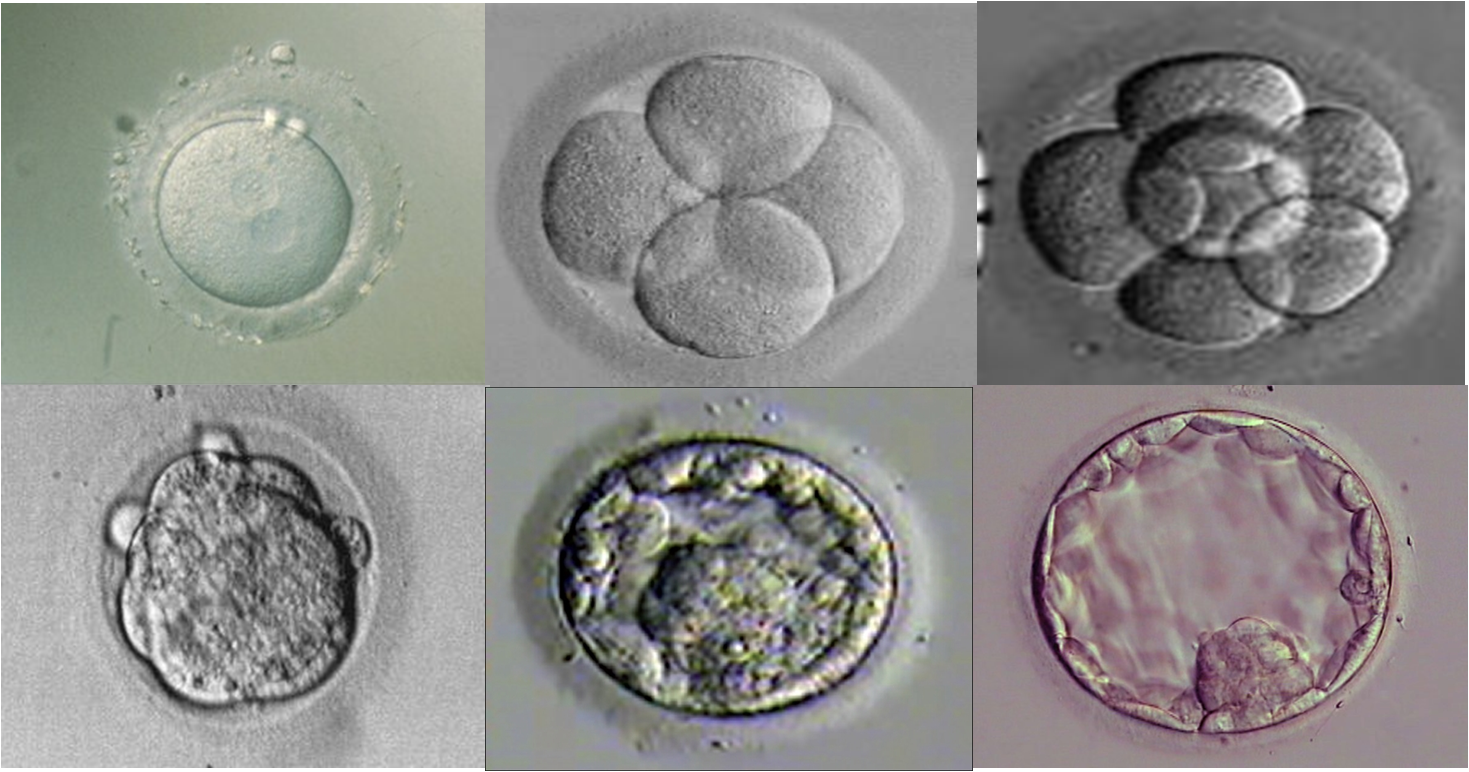

3일째 동결란 이식하는 경우 늦게 분열하는 수정란과 8세포의 수정란 사이에 임신능력의 차이는 유사하다.

2012년 유럽불임학회 (ESHRE) P-200

3일째 동결란 이식하는 경우 늦게 분열하는 수정란과 8세포의 수정란 사이에 임신능력의 차이는 유사하다.